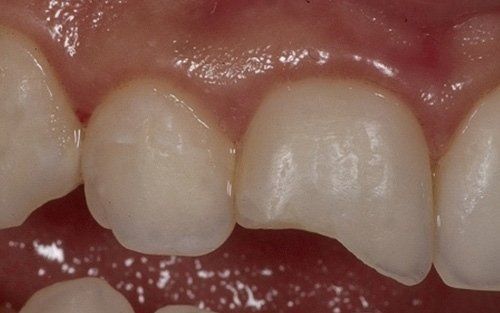

I denti da latte traumatizzati più spesso vanno incontro a necrosi con conseguente cambiamento di colore, divenendo grigiastri, segno della morte delle cellule della polpa dentaria. In altre occasioni, il dente può fratturarsi in maniera più o meno ampia: se il frammento viene ritrovato, potrà essere re-incollato in maniera invisibile, oppure verrà ricostruito con i materiali compositi.